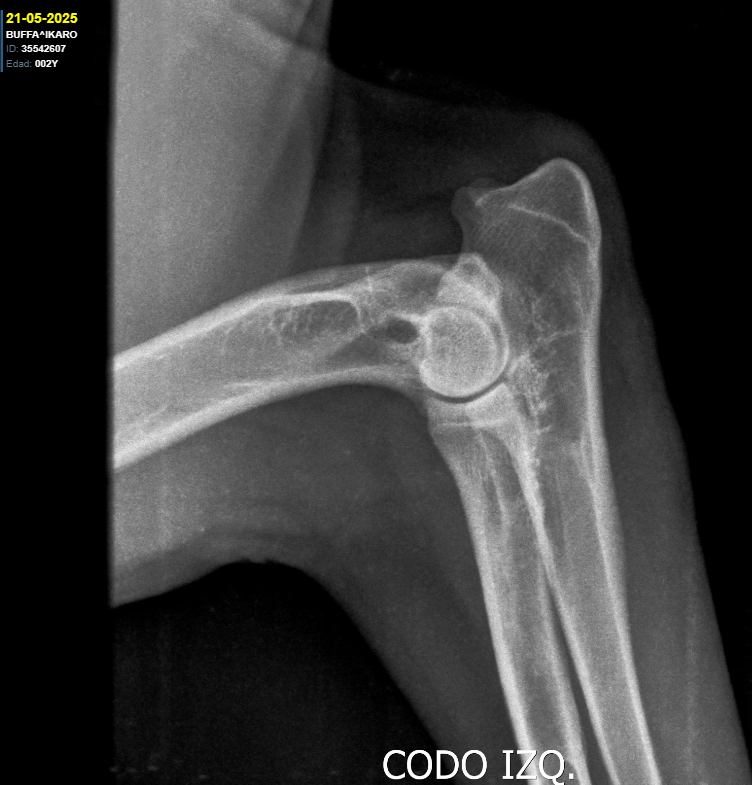

Sex: Male

Fecha de nacimiento: 21/05/2023

Pelo: Corto

Cadera y Codos:

HD A / ED 0/0

DM: N/N MDR1 +/+

Developing:

Altura: 68cm

Weight: -

Alias Íkaro, energetic, lively and determined, very dominant and self-confident, along with his brother, are partners in mischief. Íkaro is our first shorthair in the squad, a pending dream that I always waited for. He is without a doubt the perfect example of what I want to see in a shorthair. Robust and heavy build, but agile, his head is one of the most beautiful I have ever seen, with straight, strong and clean lines, excellent pigmentation, harmonious proportions and angulations and a strong forehead. He has very developed muscles for his age and it may be because he is a highly energetic dog, he is obsessed with water, rain, wind and he thinks that by attacking storms he can scare them away, he is a dream dog, without any fear.